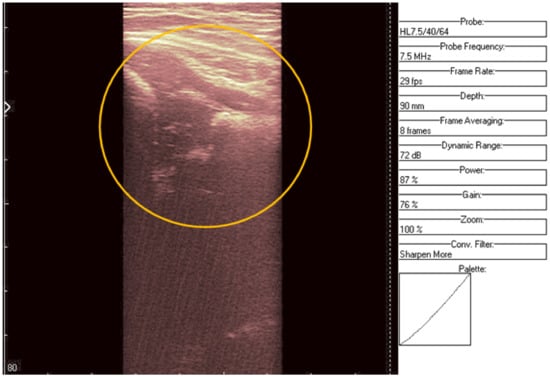

An ultrasound (Image 3 (Figure 10 and Figure 11)) was taken of a male patient with a sample frequency of 7.5 MHz and a frame rate of 29 fps. The parameters are same as in the previous two cases, yet the image of the acetabulum is hardly visible.

After applying the HWT filtering (Figure 12), the acetabulum, the femoral head, and the femur can be outlined by any physician.

We may conclude, when comparing last two images, that after filtering several details can be seen, easing the process of diagnosis for a trained physician. The denoised images are brighter and more details (not visible on the original image) can be distinguished.

Figure 4. Original data with an added color palette. A region of interest containing some speckle grains was encircled in yellow.